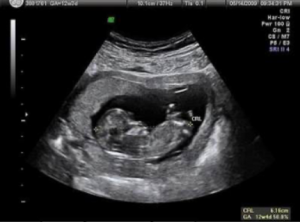

1. USG 2D

Ilustrasi USG 2D | Sumber: Kompas

USG 2D adalah jenis USG standar yang menghasilkan gambar hitam-putih datar. Meskipun tampak sederhana, USG ini adalah fondasi utama dari seluruh pemeriksaan. Dokter menggunakan USG 2D untuk:

- Mengukur biometri janin: seperti lingkar kepala (HC), lingkar perut (AC), dan panjang tulang paha (FL) untuk memantau pertumbuhan.

- Mengevaluasi organ internal: Dokter akan meneliti setiap organ vital seperti jantung, otak, ginjal, dan hati untuk mendeteksi anomali struktural. Contohnya, deteksi adanya lubang pada jantung janin atau kondisi hidrosefalus (penumpukan cairan di otak).

- Menilai posisi janin dan plasenta: Menentukan apakah plasenta berada di posisi yang aman (misalnya, tidak menutupi jalan lahir) dan memverifikasi posisi janin.